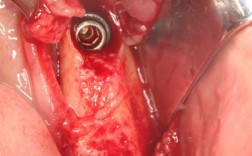

种牙自体骨植骨

种牙自体骨植骨是口腔种植修复中针对牙槽骨量不足的关键技术,指从患者自身其他部位取骨,移植到缺牙区域的牙槽骨缺损处,为种植体提供足够的骨支持,确保种植牙的长期稳定性和成功率,当牙齿缺失后,由于缺乏咀嚼刺激,牙槽骨会逐渐吸收萎缩,尤其缺牙时间较...

牙种植植骨是什么

牙种植植骨,是在患者牙槽骨量不足的情况下,通过外科手术将骨材料植入到需要种植牙的部位,以恢复牙槽骨的高度、厚度和密度,为后续种植体的植入提供足够的骨支持,确保种植牙的长期稳定和功能,这一技术是现代口腔种植修复中解决骨量不足问题的关键手段,广...